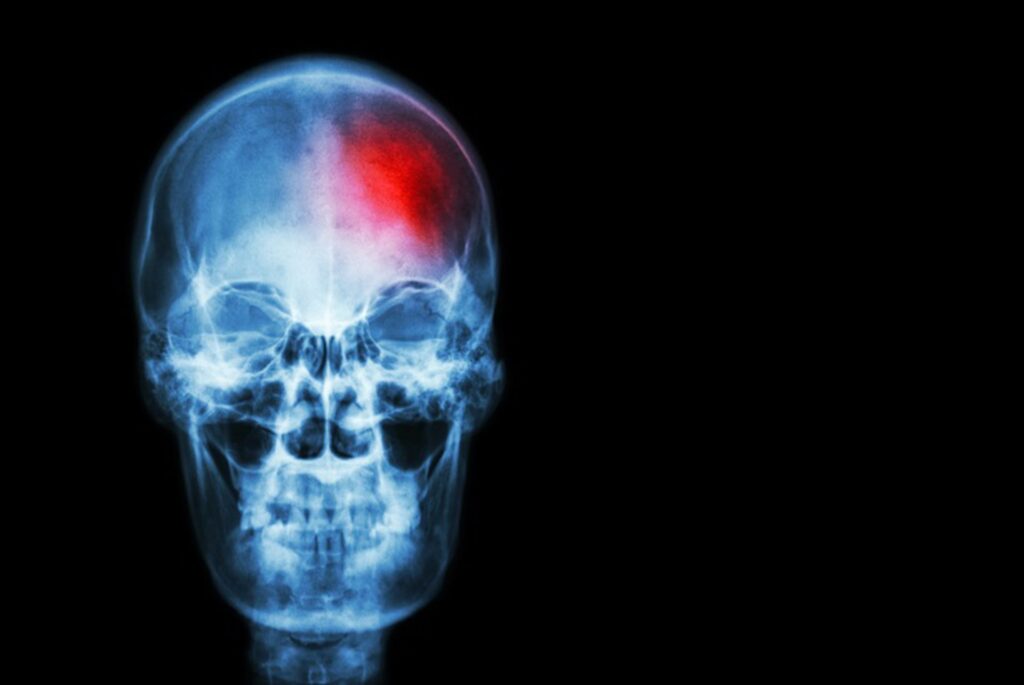

«El ictus es una enfermedad cerebrovascular que se produce cuando el flujo de sangre que llega al cerebro se interrumpe o se reduce. Existen dos tipos principales de ictus: el ictus isquémico, que representa aproximadamente el 80% de los casos, y el ictus hemorrágico, que supone el 20% restante. Mientras que el ictus isquémico se produce cuando un trombo impide u obstaculiza la llegada de sangre al cerebro, el ictus hemorrágico se genera por la rotura de alguno de los vasos sanguíneos del cerebro. Pero en ambos casos el tiempo de actuación es determinante», explica la doctora Mª Mar Freijo, Coordinadora del Grupo de Estudio de Enfermedades Cerebrovasculares de la SEN.